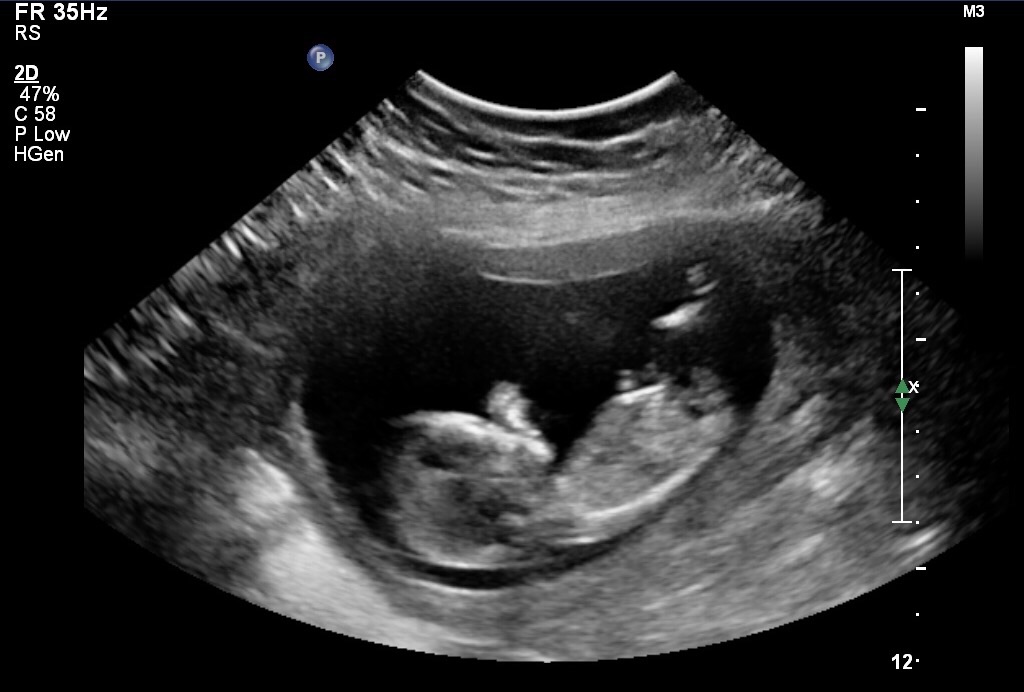

Was hoping for a better pic so not sure what part is the nub can anyone help me please Attachment 34197Attachment 34198